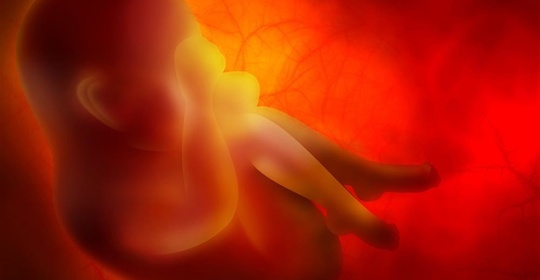

正弦胎心率:孕期小百科,詳細瞭解胎心率異常與預防!

胎兒水腫:孕期健康提醒,關愛寶寶發育的每一步!

胎勢異常:關注胎兒健康,瞭解胎兒體位問題及調理!

胎心不規則:孕期安全須知,提前瞭解及時防範!

胎兒發育遲緩:瞭解問題,關注孕期,科學保護胎兒!